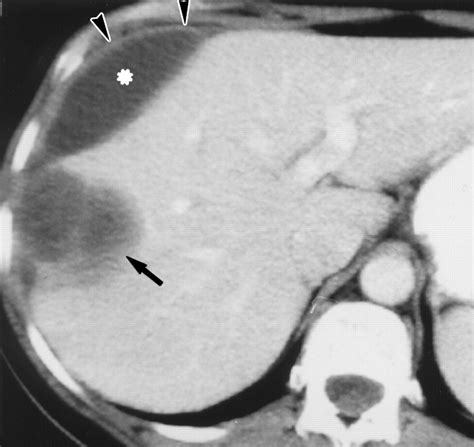

Diagnosing a liver abscess involves a combination of medical history, physical examination, and diagnostic tests. Imaging studies such as ultrasound, CT scans, and MRI are commonly used to visualize the abscess. Blood tests can help identify the underlying infection, and sometimes, a sample of the abscess fluid may be taken for culture and sensitivity testing.